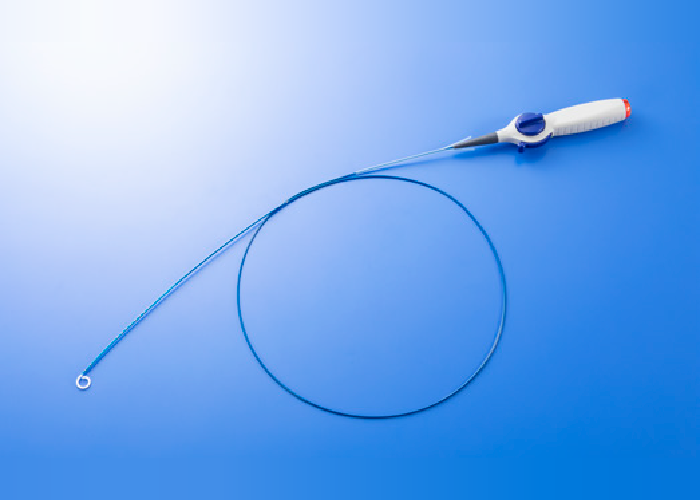

ルーメン付き電極カテーテル

- 販売名

- カネカ ルーメン付き電極カテーテル

- 医療機器承認番号

- 30500BZX00106000